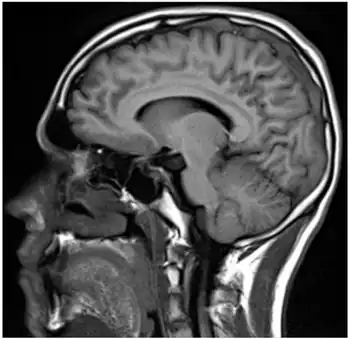

| Sagital-Prothrombin G20210A as cause of cerebral venous thrombosis | |